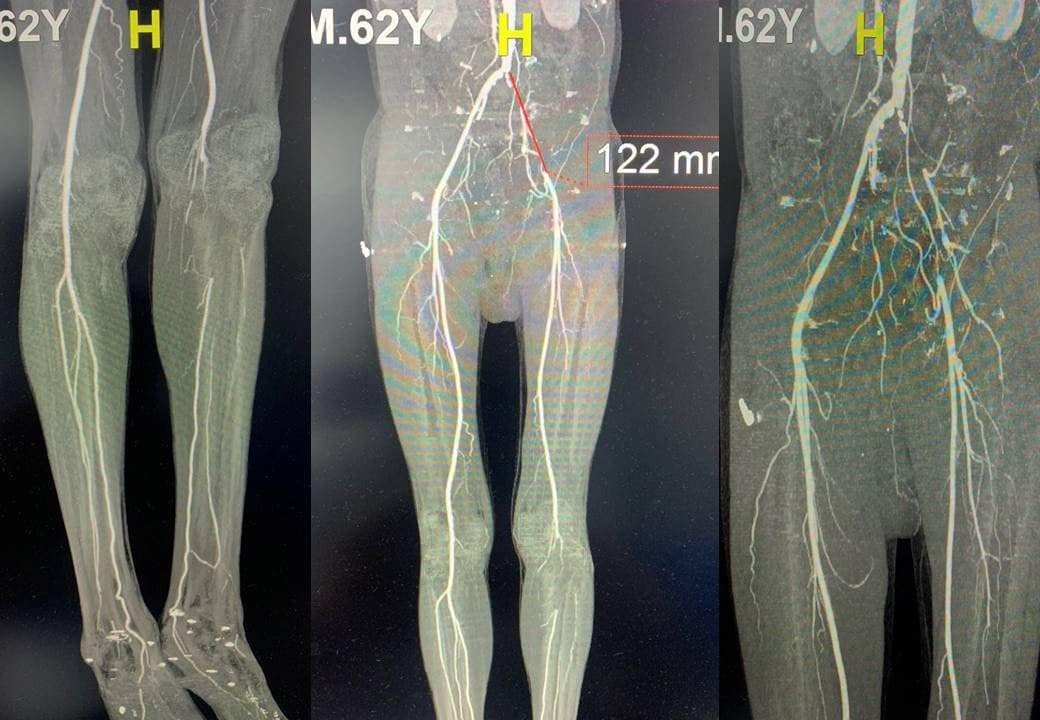

Bệnh nhân là cụ ông T.T.S., 81 tuổi, quê ở Nghệ An, nhập viện trong tình trạng đau dữ dội, các ngón chân phải bị hoại tử. Kết quả thăm khám cho thấy người bệnh bị hẹp động mạch chậu hai bên, tắc động mạch đùi nông phải, kèm theo tình trạng xơ vữa và vôi hóa mạch máu lan tỏa.

Ban đầu, các bác sĩ tiến hành can thiệp nội mạch và nong thành công động mạch chậu trái. Tuy nhiên, hệ mạch bên phải bị vôi hóa nặng nên không thể tái thông hoàn toàn bằng phương pháp này.

Trước tình trạng phức tạp, ê-kíp điều trị đã chuyển sang phẫu thuật nhiều giai đoạn, thực hiện bắc cầu động mạch đùi trái - đùi phải, đồng thời bóc nội mạc động mạch đùi phải nhằm tái lập dòng máu xuống chi. Sau phẫu thuật, tình trạng tưới máu được cải thiện rõ rệt, bàn chân dần hồng trở lại. Người bệnh có thể đi lại, sinh hoạt bình thường và đã được xuất viện. Trường hợp này là lời cảnh báo rõ ràng về mức độ nguy hiểm của bệnh nếu không được phát hiện sớm.